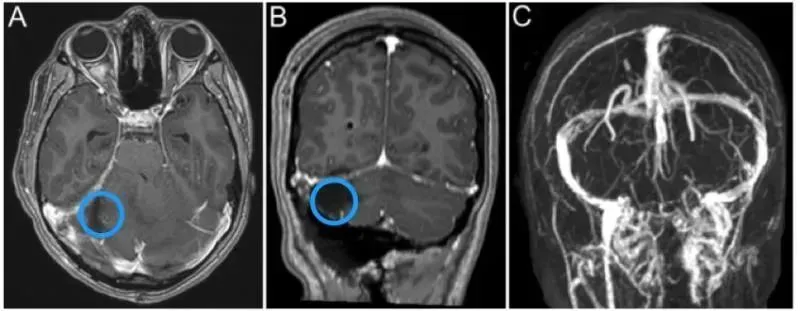

术前影像显示肿瘤侵犯右侧横窦。C冠状位影像显示右侧小脑半球肿瘤侵犯右侧横窦。

当检查结果出来的那一刻,Cathy的父母如遭雷击:她右侧小脑半球有一个巨大占位:尺寸约5.6×5.0×3.4cm——宛如一颗鸡蛋藏在脑中。第四脑室也变得狭窄,还出现了梗阻性脑积水,初步诊断为恶性髓母细胞瘤。

更棘手的是,肿瘤已侵犯右侧横窦,这是颅内重要的静脉回流通道,若手术中为了切除肿瘤而损伤横窦,可能引发大出血、静脉窦血栓等严重并发症,甚至直接导致手术失败。